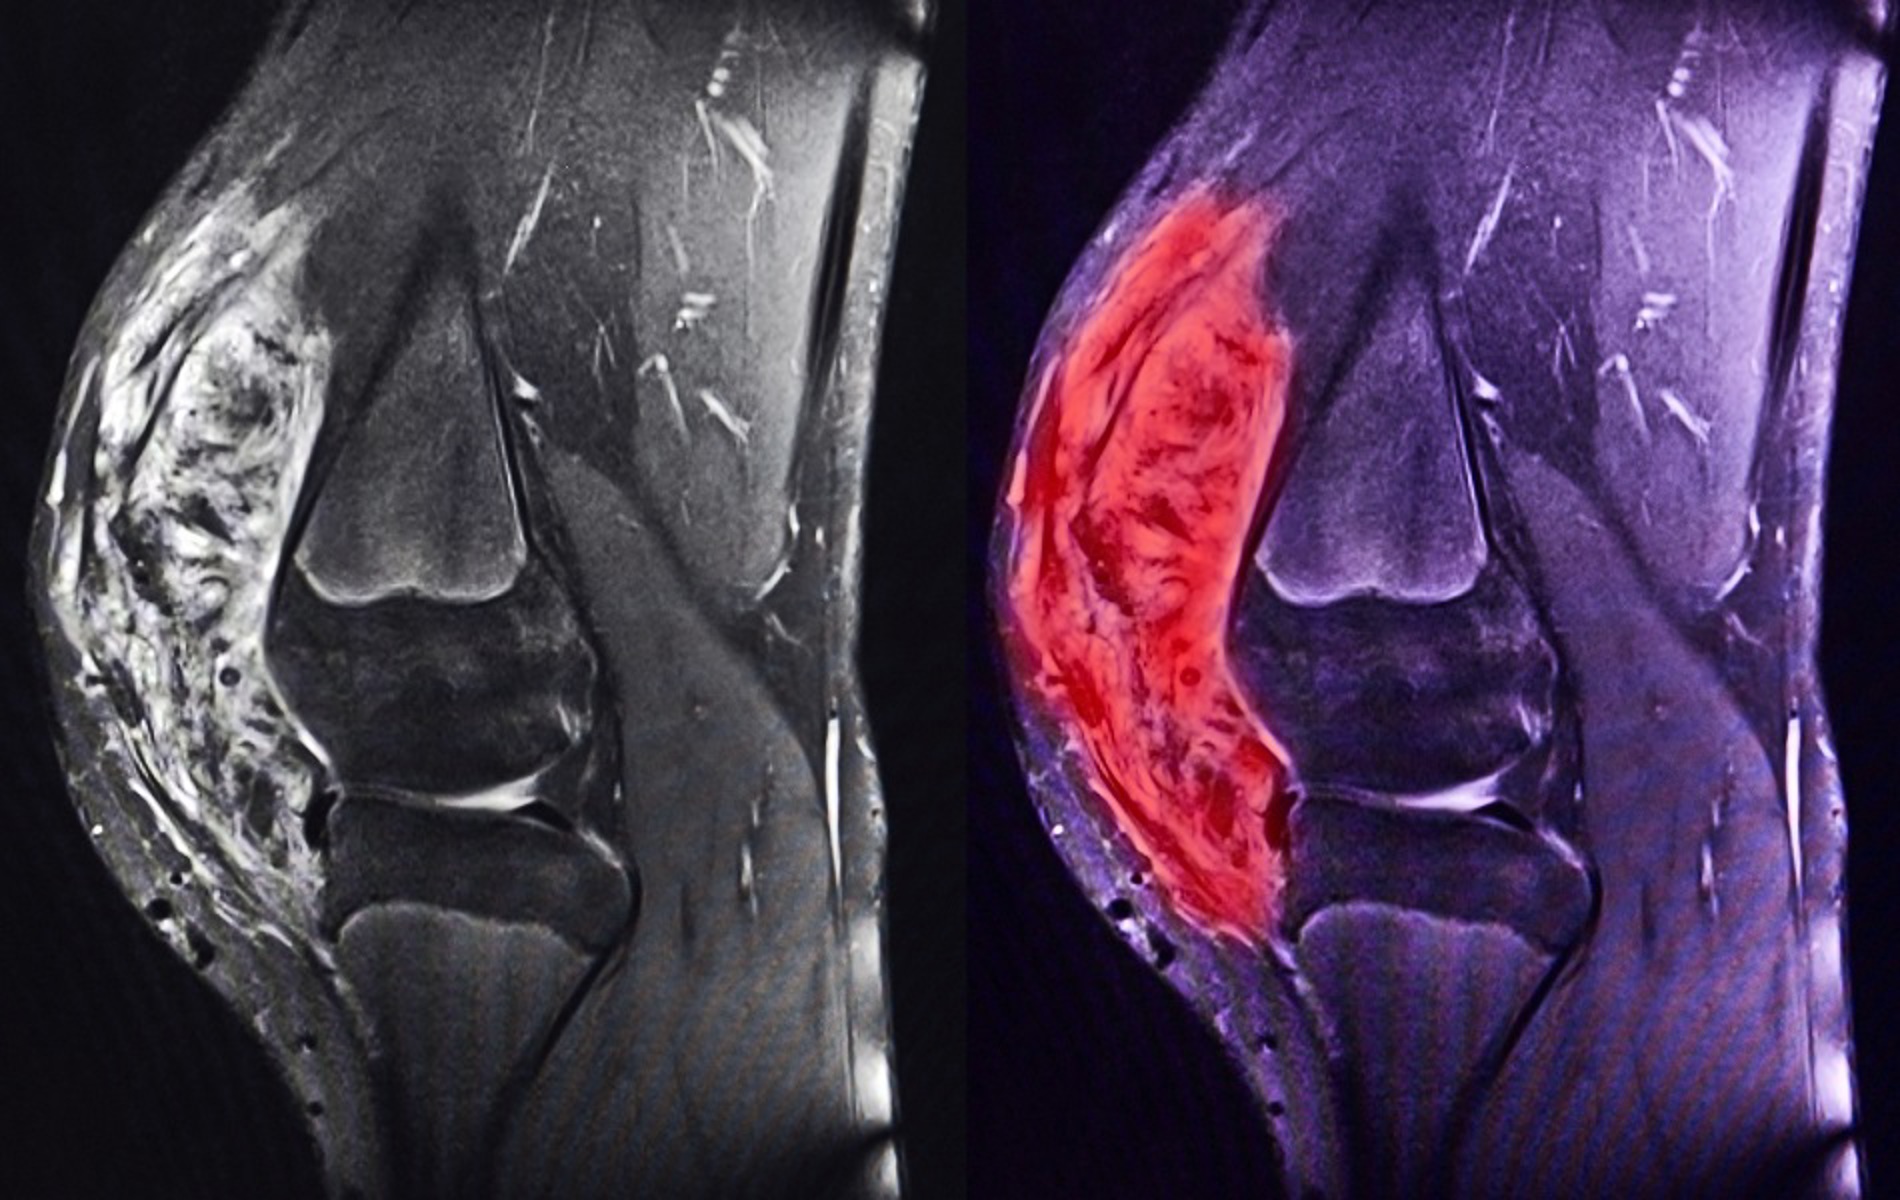

| 09:25 | Radiology Dr Anand Kirwadi, Manchester Foundation Trust |